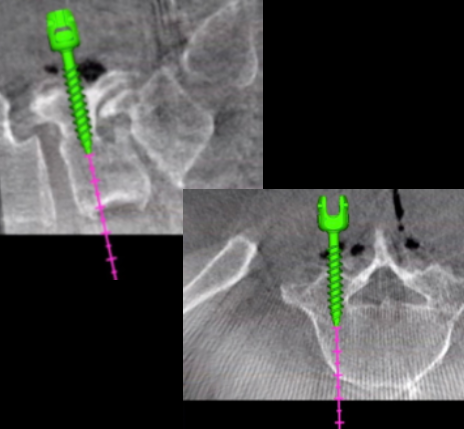

CIRURGIA ROBÓTICA

As novas tecnologias de navegação e uso de braço robótico na cirurgia de coluna auxiliam o passo a passo na implantação de dispositivos para artrodese (fixação com espaçadores e parafusos de coluna).

CIRURGIA DE ARTRODESE PARA DOENÇAS DEGENERATIVAS

A fixação das vértebras pode ser feita em qualquer segmento da coluna – cervical, torácica ou lombar. As cirurgias podem ser feitas pela frente, pela lateral ou por trás, ou então, por vias combinadas.